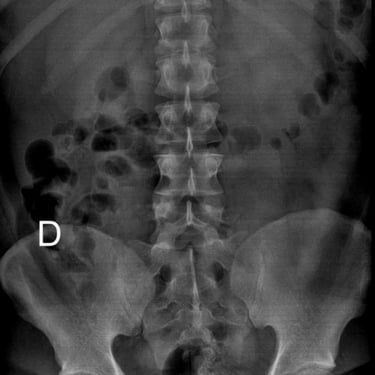

Listesis Lumbar L5–S1 por Fractura Ístmica: Estabilización con FTP y TLIF

La listesis lumbar L5–S1 por fractura ístmica se produce por un defecto en la pars interarticularis que genera inestabilidad vertebral, dolor lumbar crónico y compromiso radicular. Cuando el tratamiento conservador no es efectivo, la artrodesis lumbar con fijación transpedicular (FTP) asociada a la fusión intersomática transforaminal (TLIF) es una alternativa quirúrgica eficaz. Este procedimiento permite descomprimir las raíces nerviosas, restaurar la alineación vertebral y lograr una fijación sólida del segmento afectado. La combinación de estabilización y fusión reduce el dolor, mejora la función y favorece una recuperación segura y progresiva.